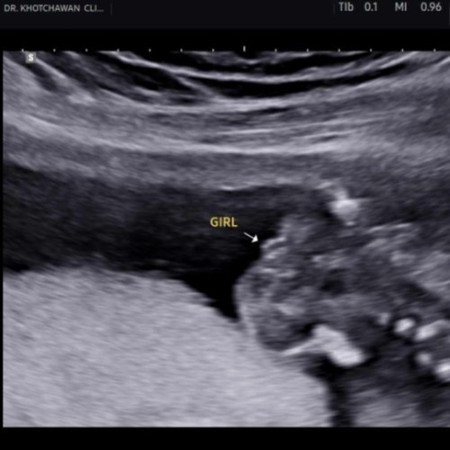

หญิงหรือชาย

หมอบอกว่าน้องน่าจะเป็นผู้หญิง แต่แม่ไม่มั่นใจเลยเพราะเห็นไม่ชัด น้องนอนขดเอาหัวทิ่มลงมา แล้วแม่ๆคิดว่าไงคะหญิงหรือชาย ใจนึ่งแม่ก็คิดว่าหญิงแต่ดูไปดูมาก็เหมือนชาย รบกวนแม่ๆช่วยดูหน่อยน๊าา 17w6d